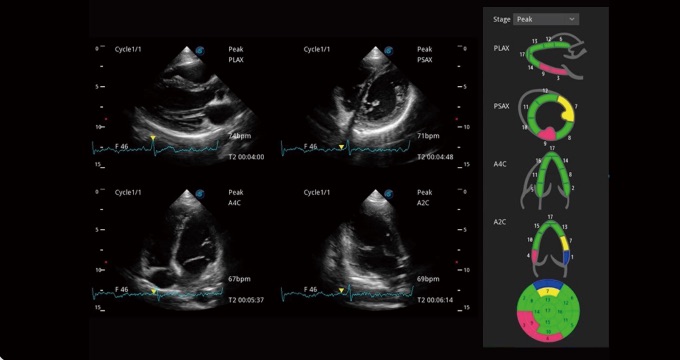

• Stress Echo

Una plantilla sencilla para que los médicos tomen múltiples imágenes dinámicas en reposo y después del estrés y realicen una comparación paralela. Se proporcionan calificaciones y reportes profesionales y precisos del movimiento de pared para una evaluación más efectiva de la viabilidad del músculo cardíaco.

• Análisis Cuantitativo del Miocardio (MQA)

La medición cuantitativa precisa de la mecánica del miocardio se logra mediante un MQA basado en el monitoreo sensible del movimiento de la pared en tiempo real. Proporciona una evaluación global y regional que incluye deformación, tasa de deformación, desplazamiento, velocidad, etc.